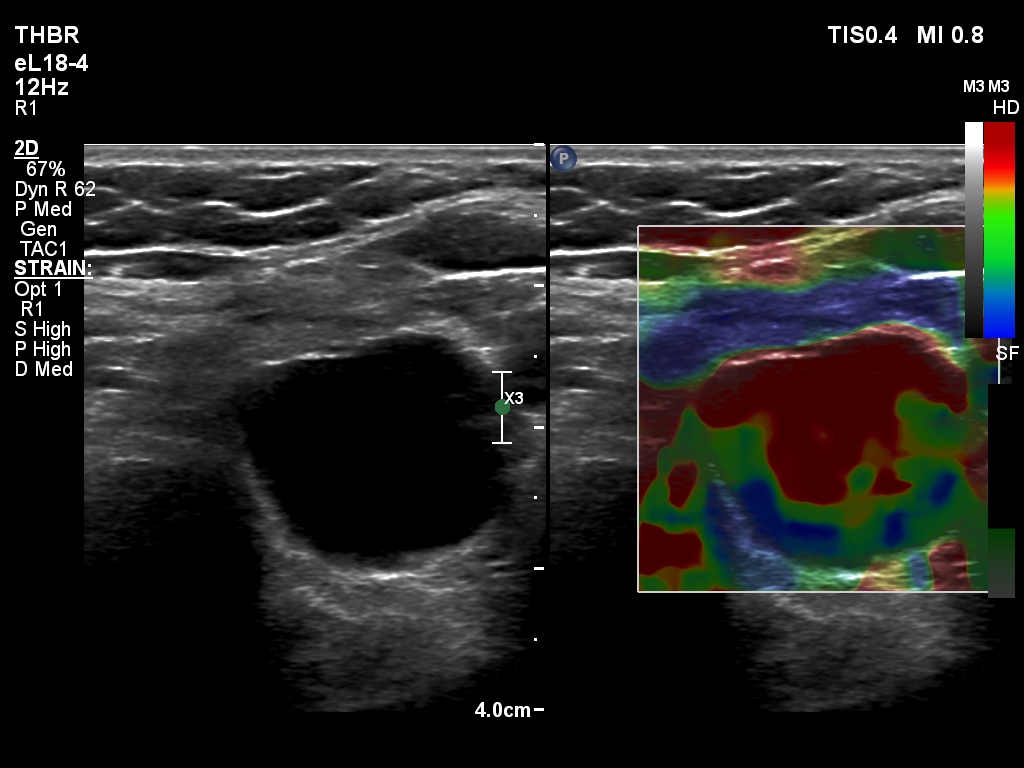

The composition of the nodule - case 2179 (ultrasonographic picture 22)

Right lobe, longitudinal scan

Lower part of the left lobe, transverse scan, elastography. Elastography has no sense in the event of a dominantly cystic nodule.